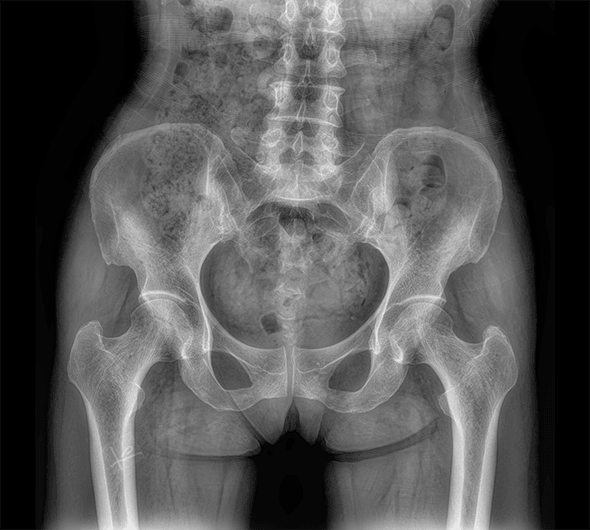

临床图像